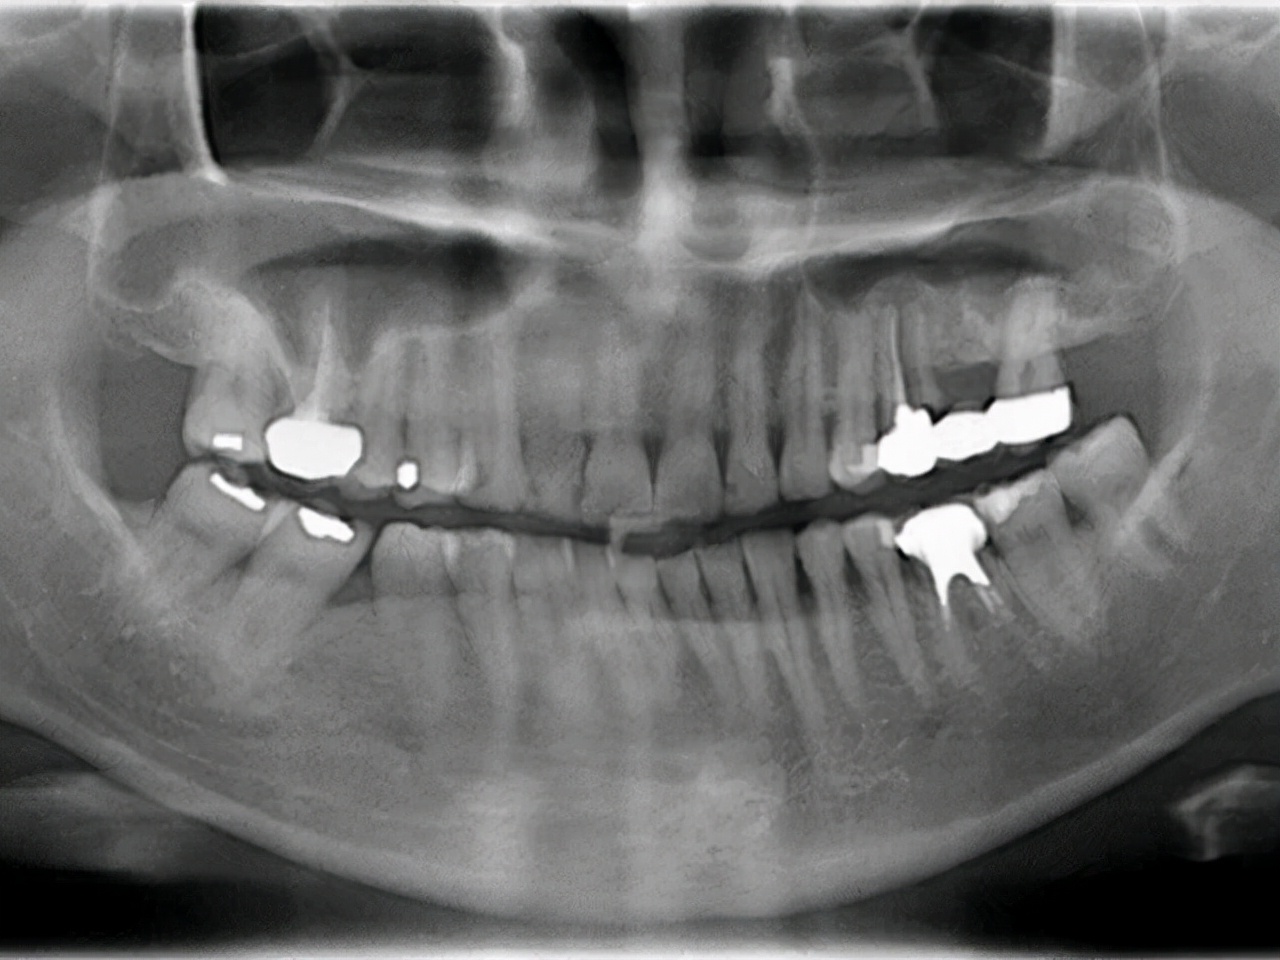

如图所示:左上牙根断裂